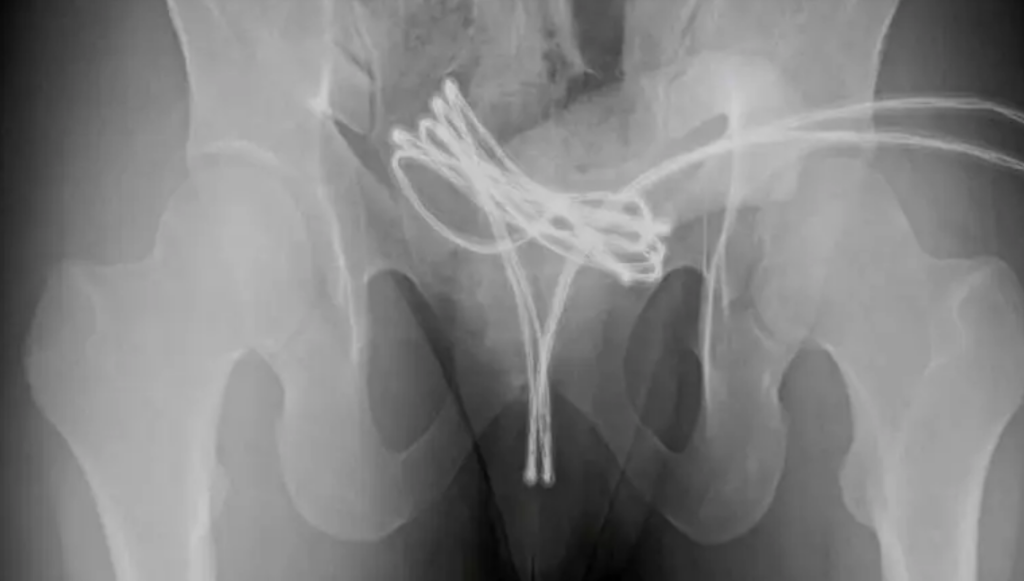

De acuerdo con el medio en mención, al no poder retirar el objeto por sus propios medios, el joven acudió a un centro médico donde las radiografías revelaron que el cable USB se había alojado profundamente en la vejiga y se encontraba doblado, lo que dificultaba su extracción.

El equipo médico de la Facultad de Medicina de la Universidad Drexel, en Pensilvania, trasladó al paciente al quirófano para realizar la intervención quirúrgica.

Los especialistas extrajeron el cable mediante cirugía bajo anestesia general, sin mayores complicaciones. El joven sufrió heridas menores y recibió el alta tras recuperarse satisfactoriamente.